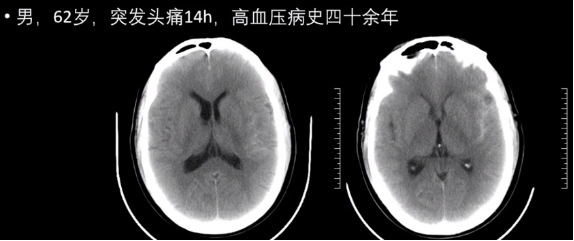

病因:高血压、动脉瘤、血管畸形、脑肿瘤。

常见部位:内囊基底节、丘脑;其次小脑、脑干、蛛网膜下腔。

病理分期:急性期(1 周内);吸收期(第 2 周~2 月);囊变期(&2 月)。

2.脑出血影像学表现

信号特征复杂,与血管内红细胞的完整性及血红蛋白的演变有关。